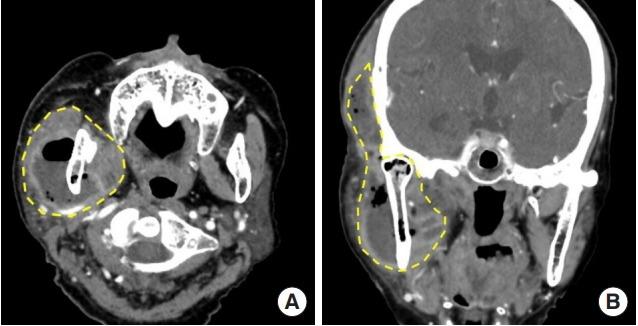

Necrotizing fasciitis of the masticator space with osteomyelitis of the mandible in an edentulous patient.

Secondary craniofacial necrotizing fasciitis from a distant septic emboli: A case report.